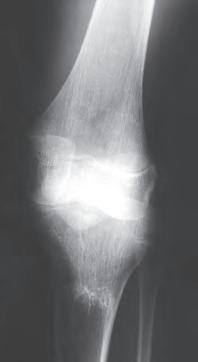

Rycina 17.82.

Uszkodzenie tętnicy podkolanowej wskutek złuszczenia nasady bliższej kości piszczelowej (S-H 1). Zagrożenie rozwojem zespołu przedziałów powięziowych jest poważne.

Rozpoznanie

Objawy złamania to silny ból uniemożliwiający stanie i chodzenie, zniekształcenie obrysów stawu kolanowego przez krwiak i różnego stopnia przemieszczenie nasady kości piszczelowej. Należy dokładnie zbadać stan ukrwienia i unaczynienia kończyny pod kątem objawów uszkodzenia tętnicy podkolanowej i nerwu strzałkowego. Trzeba ocenić bolesność uciskową oraz napięcie w przedziałach powięziowych podudzia: przednim, bocznym, tylnym powierzchownym i tylnym głębokim. U pacjentów z podejrzeniem wzmożonego ciśnienia wewnątrzprzedziałowego należy wielokrotnie powtarzać badanie ukrwienia i unerwienia kończyny, a w razie zaistnienia wskazań wykonać bezpośredni pomiar ciśnienia w przedziałach. Powinno się zawsze podejrzewać możliwość uszkodzeń więzadłowych współistniejących ze złamaniem. Badania obrazowe to RTG w pozycji AP, bocznej i skośnej. Wykonanie badania TK może być konieczne w celu pełnej oceny rozległości

złamania. W przypadku podejrzenia uszkodzenia tętnicy podkolanowej należy wykonać angio-TK lub arteriografię.

Leczenie

Leczenie złamania bliższej nasady piszczeli w przypadku uszkodzenia typu 1 i 2 według Saltera i Harrisa leczymy nieoperacyjnie. Należy wykonać zamkniętą repozycję i unieruchomić w opatrunku gipsowym udowym w zgięciu kolana 30–60°, zapewniającym najlepszą stabilność odłamów. Okres unieruchomienia wynosi od 6 do 7 tygodni. Po tym czasie usuwamy gips i zaczynamy ćwiczenia zwiększające zakres ruchomości stawu kolanowego oraz wzmacniające siłę mięśnia czworogłowego. Ważne jest, by prowadzić częste kontrole stanu ukrwienia i unaczynienia oraz kontrole radiologiczne w celu wykrycia ewentualnych przemieszczeń odłamów. Złamania pierwotnie niestabilne lub wtórnie przemieszczone wymagają zamkniętej repozycji stabilizacji drutami K. Typ 3 i 4

Złamania rzepki i podudzia

złamania według Saltera i Harrisa wymaga leczenia operacyjnego w postaci otwartej repozycji i stabilizacji śrubami. Należy unikać krzyżowania metalu zespalającego z chrząstką wzrostową. Kończynę zgiętą w kolanie do 30° unieruchamia się w gipsie udowym na okres 6–8 tygodni. Po tym czasie rozpoczynamy ćwiczenia czynne poprawiające zakres ruchomości kończyny.

Powikłania

Zespół ciasnoty przedziałów powięziowych

Zespół ciasnoty przedziałów powięziowych może wystąpić wskutek uszkodzenia tętnicy podkolanowej (10% przypadków). Wynika on ze ścisłego powiązania tętnicy z torbą stawową na wysokości proksymalnej części piszczeli. Należy ściśle monitorować stan kończyny i unikać okrężnych opatrunków gipsowych.